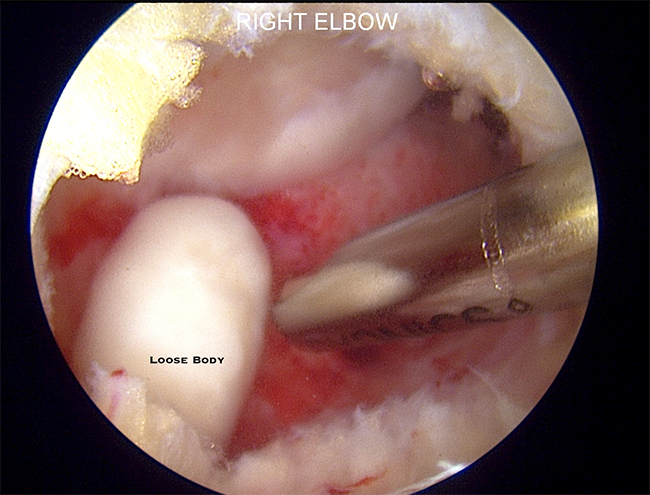

- Removal of Loose Bodies

- Small fragments of bone or cartilage can dislodge and float inside the joint. These can arise from injury or repetitive stress associated with throwing

- These loose fragments can cause pain, locking, catching or loss of motion in the elbow

- Elbow arthroscopy can remove free floating fragments from within the joint through small incisions

Dr. Nelson performing arthroscopic removal of loose body from the elbow

Arthroscopic Removal of Loose Body